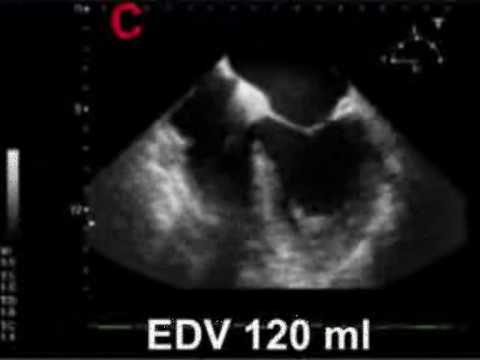

2. 21ABC. LV performance & Stroke Volume assessment (WINFOCUS, CC ECHO Course, by Gabriele Via) :

how to assess volume status